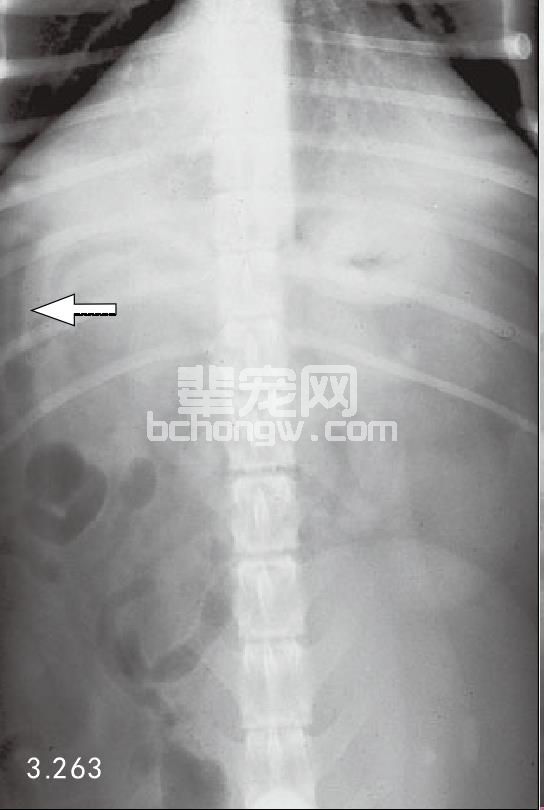

两种最常用方法是X线和超声波。犬和猫急性胰腺炎的腹部X线能显示几处异常。在轻度水肿时,可见包括 胃和十二指肠从正常到轻度肠梗阻范围。更严重时,由于腹膜炎会导致以下变化:在腹腔前部由于液体密度增 加,使内脏详细影像消失,右侧十二指肠移位和胃扩张。除这些典型症状外,急性胰腺炎X线显示胸腔渗漏液和 肺部积液(图3.262和图3.263)。

图3.262和图3.263 犬患有急性胰腺炎的几种异常的侧面和腹背面的X线片,侧面投影(图3.262)显示腹中前部不清楚,腹前部液体密度增加,从末 端到肝脏(箭头所指)。腹背面X片(图3.263)可见与十二指肠梗阻一起,单侧右上腹部液体密度增加。